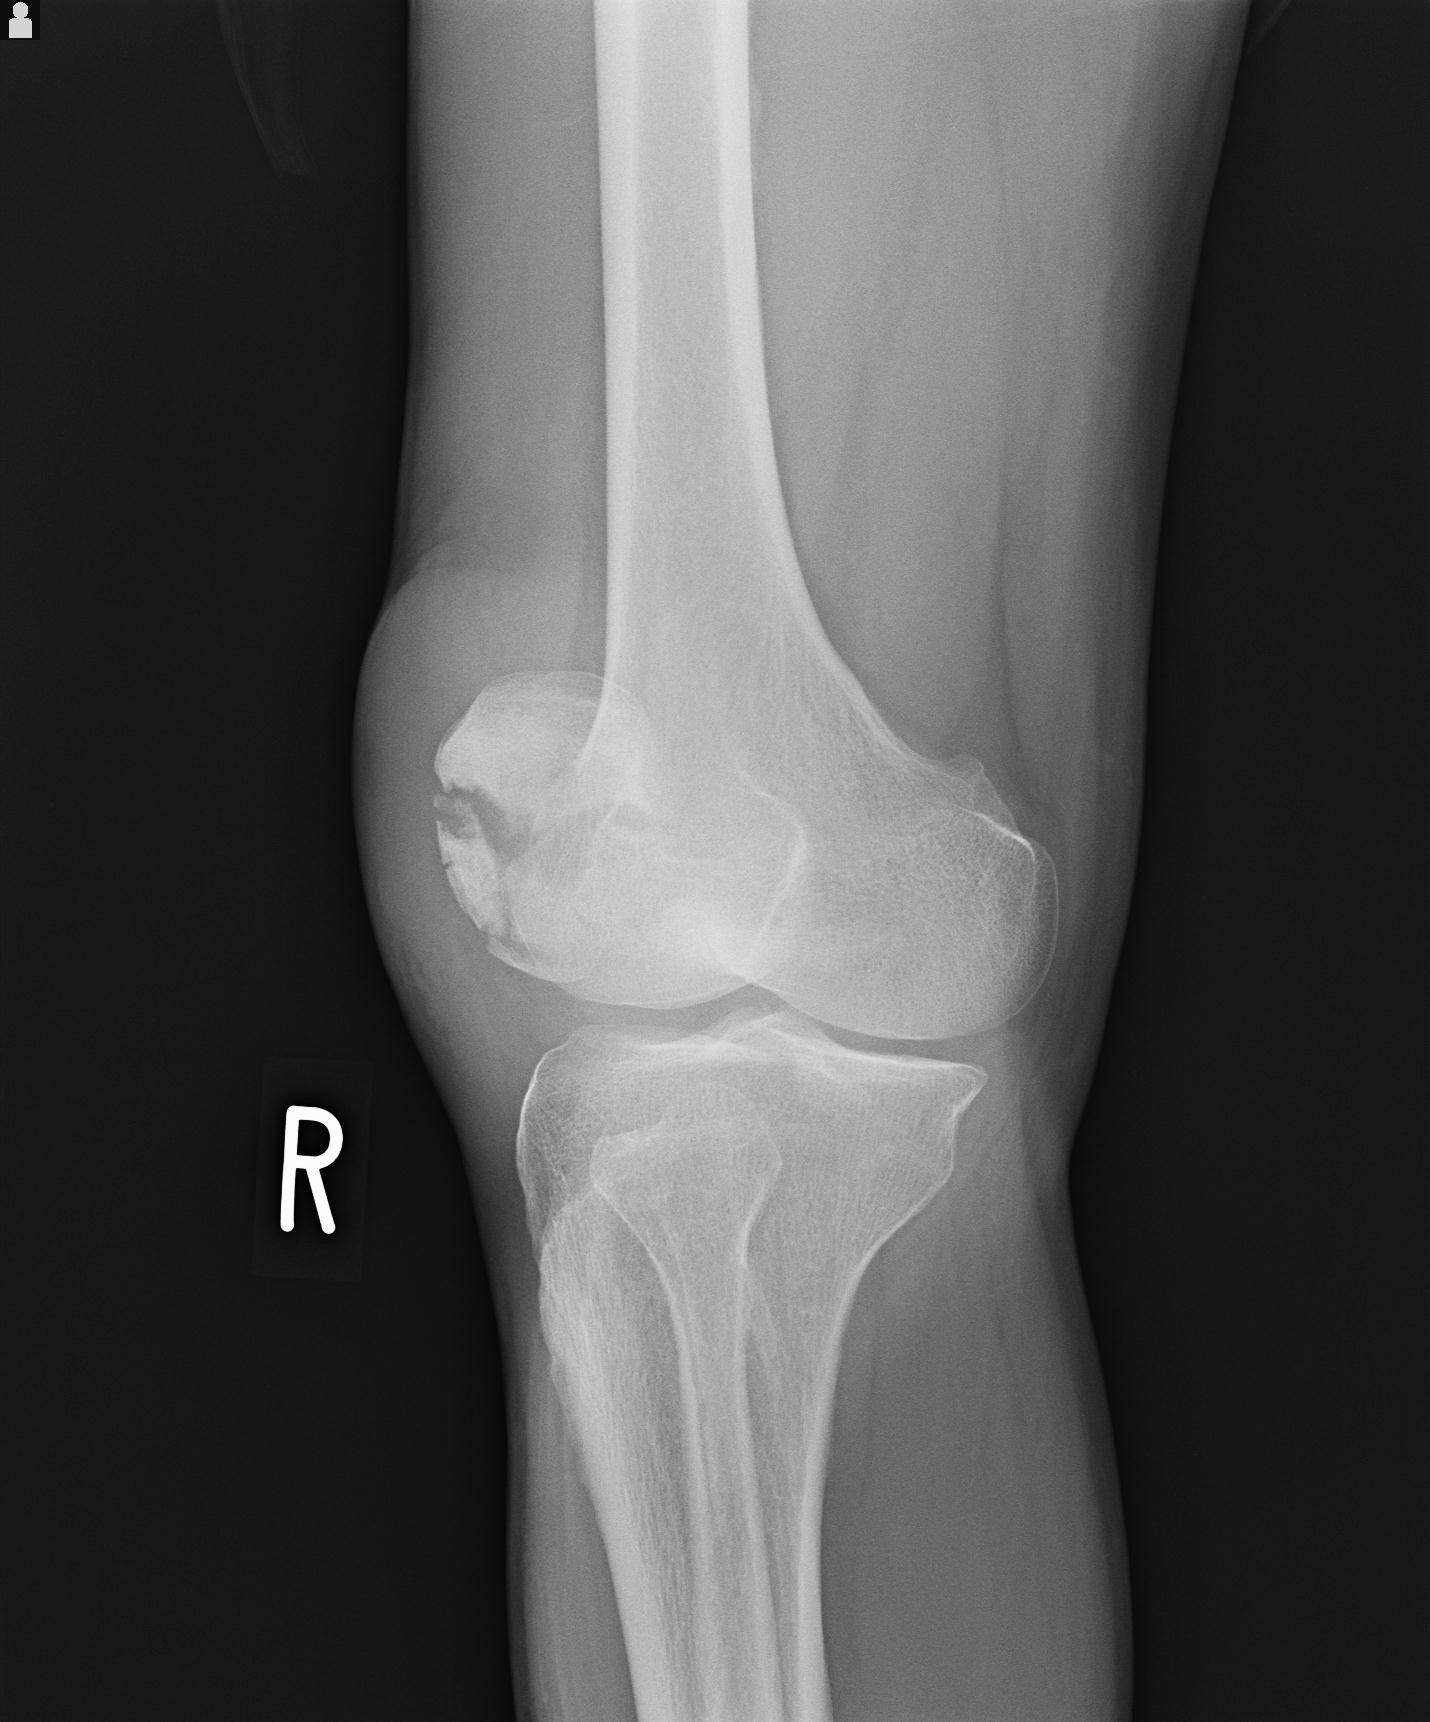

49554 3/13 膝 4R 3/16 4R 1/18 2R 78歳男性 膝蓋骨骨折